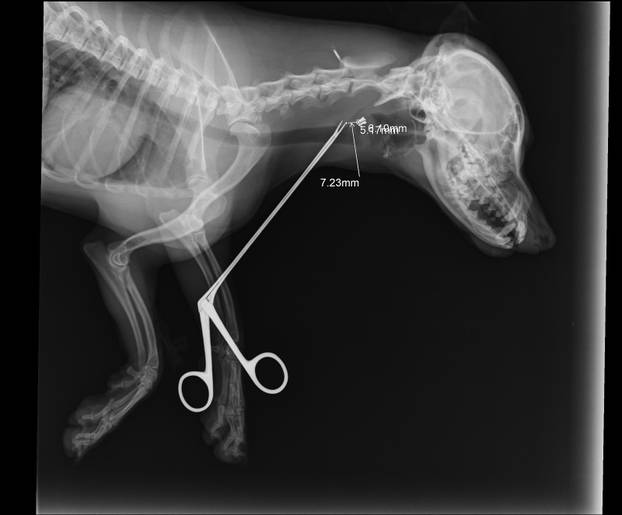

Metak je visoko gore i duboko kod kralješka. Zbog izazivanja većih lezija odustalo se od vađenja metka - stoji u nalazu kujice Lene

- Lena se ponašala najnormalnije. Vidjeli smo krv tek kod kuće. Odmah smo je odveli veterinaru u Pakrac, ali uputili su nas dalje u Daruvar na rendgen. Veterinar Karaula je tada vidio da je metak zapeo i pokušao ga izvaditi pincetom. Svim silama se trudio i bio nadomak metka, ali uvijek je malo falilo. Metak je zapeo kod kralješka, jako duboko. Bilo mu je krivo, kaže da je to prvi put da nije uspio. Da je dalje pokušavao, riskirao bi oštećenje živca, a to ne bi bilo dobro - priča nam vlasnica.

- Metak mu je došao jako blizu kralješka pa sam odlučio da je najbolje da ga ne diramo. Moglo bi biti opasno. Za dlaku je izbjegao veću nesreću - mogao je ostati paraliziran. Već sljedeći dan došli su na pregled kod mene, a Lena je bila vesela i razigrana. Ma, kao da je na baterije - priča nam doktor Karaula.

- Sinoć tijekom šetnje pas se trznuo, a kada su došli kući vidjeli su krv iz vrata. Bili su u stanici Pakrac i tamo su obradili ranu. Metak je veličine dijabole 6,10 - 5,16 mm. Metak je visoko gore i duboko kod kralješka. Zbog izazivanja većih lezija odustalo se od vađenja metka - stoji u nalazu kujice Lene.